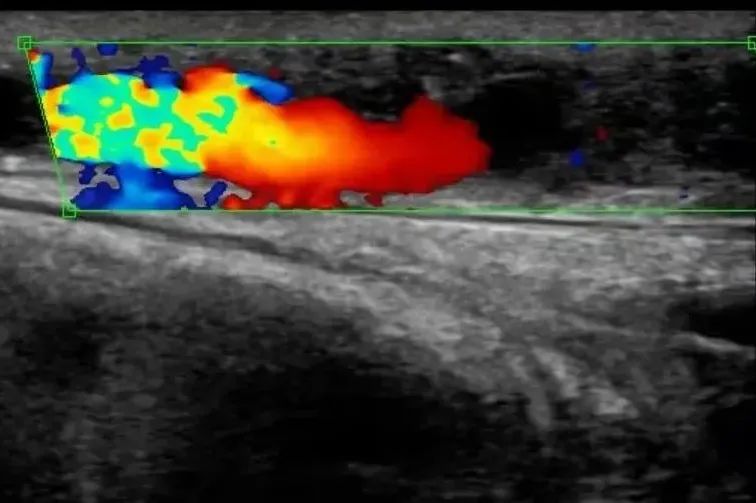

术前B超显示静脉血栓形成、狭窄闭塞

▲术后B超显示血流畅通